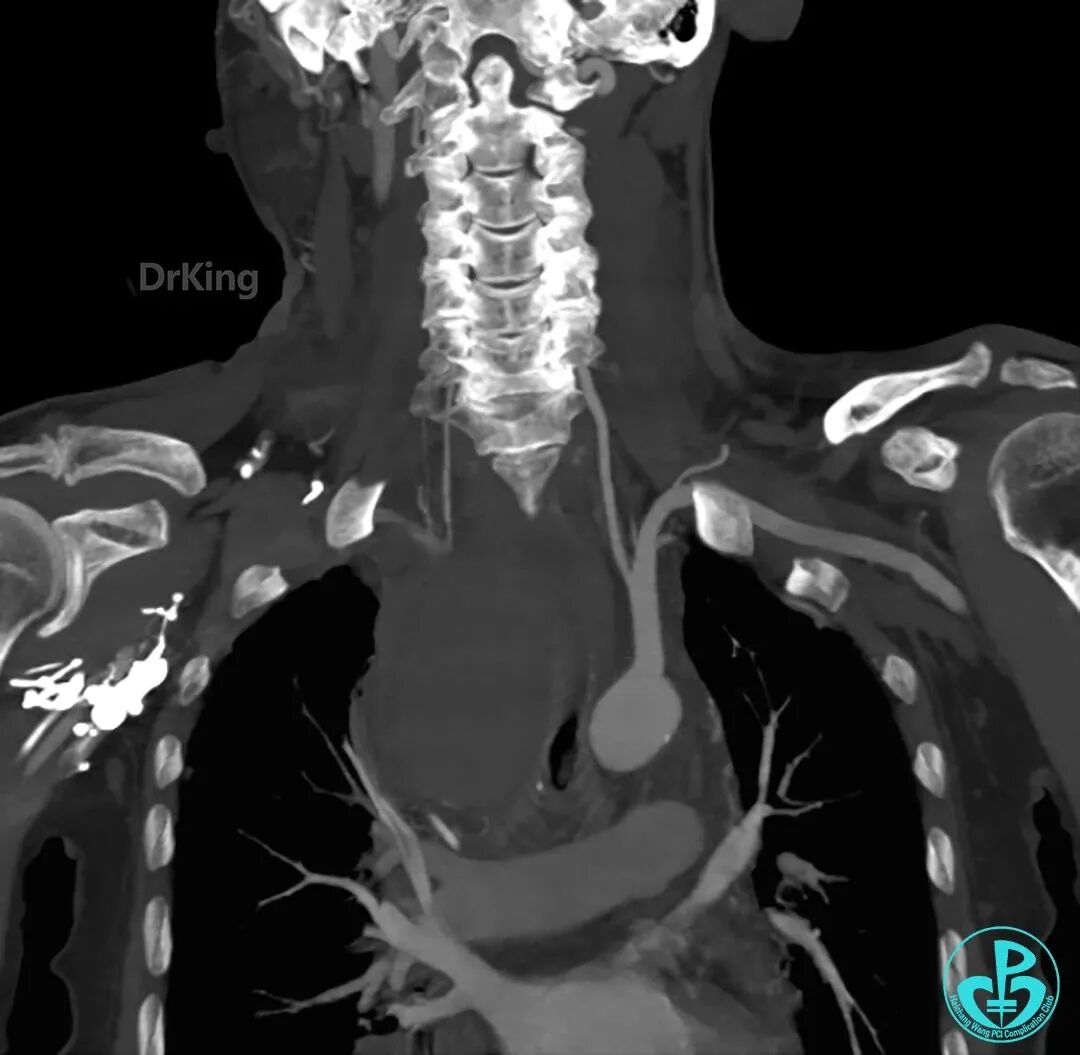

术后CTA未发现异常。

泥鳅导丝怎么用超滑泥鳅导丝致纵隔血肿,保守治疗血肿吸收_https://www.jmylbn.com_新闻资讯_第18张

泥鳅导丝怎么用超滑泥鳅导丝致纵隔血肿,保守治疗血肿吸收_https://www.jmylbn.com_新闻资讯_第19张